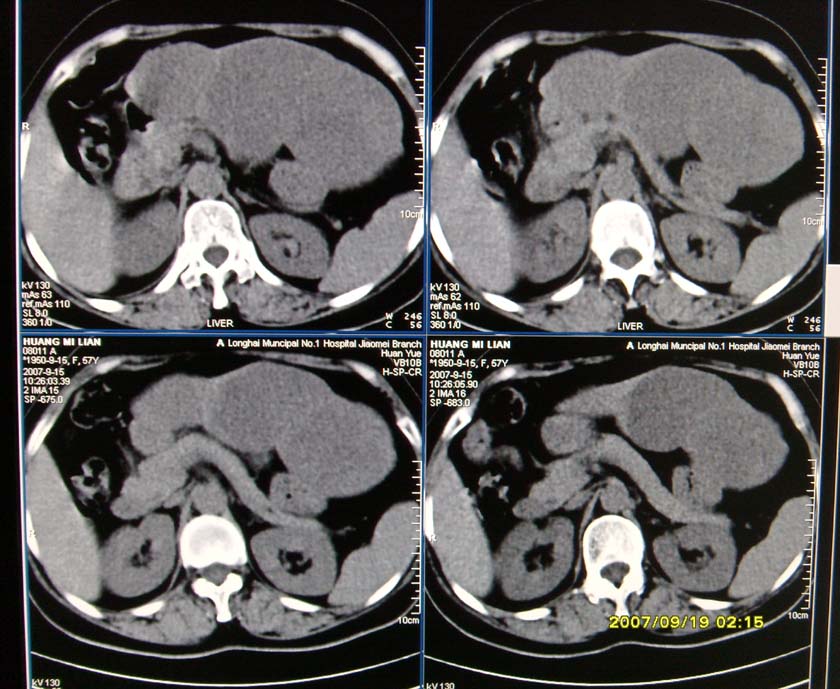

以下是引用逸风在2007-9-19 20:11:00的发言:[br]定位在肝左叶应该没有问题![br]ct显示肝左叶巨大低密度病灶,ct值30hu,密度欠均匀,里面似可见更低密度区;肝门及腹膜后未见明确肿大淋巴结.其与胃之间脂肪间隙存在;彩超提示病灶多发.[br]我个人觉得首先应该增强扫描,从平扫所见结合超声,首先应该考虑血管瘤.

以下是引用davisxuyong在2007-9-19 16:29:00的发言:[br]肝左叶大片状低密度灶,肝癌待排,建议增强。